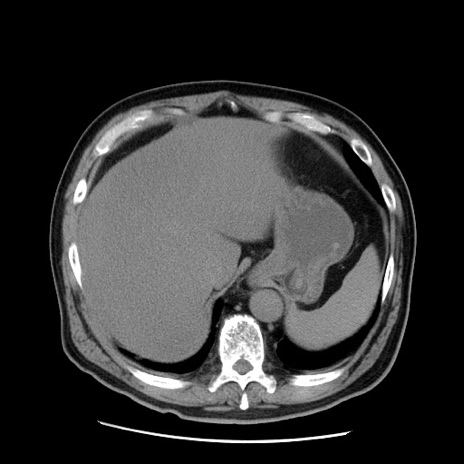

症例20(横断像)

【症例】 60歳代男性

【主訴】 腹部膨満、嘔吐

【現病歴】5日前頃より倦怠感を認め食事量減少し4日前の朝嘔吐、食事摂取困難となった。 3日前近医受診し点滴施行され整腸剤などを処方された。 当日他院を受診し、腹部膨満著明、炎症反応の上昇(CRP10.8、WBC11200)あり、紹介受診となる。

【身体所見】 意識JCS1 受け答えがはっきりしないBP 111/57mHg、 P 67bpm、、BT35.2°C、SpO2 97%(RA)、 腹部:膨隆、打診で鼓音あり、全体的に圧痛有り、腸蠕動音(-)、反跳痛ははっきりせず。

【データ】WBC 11400、CRP 14.20